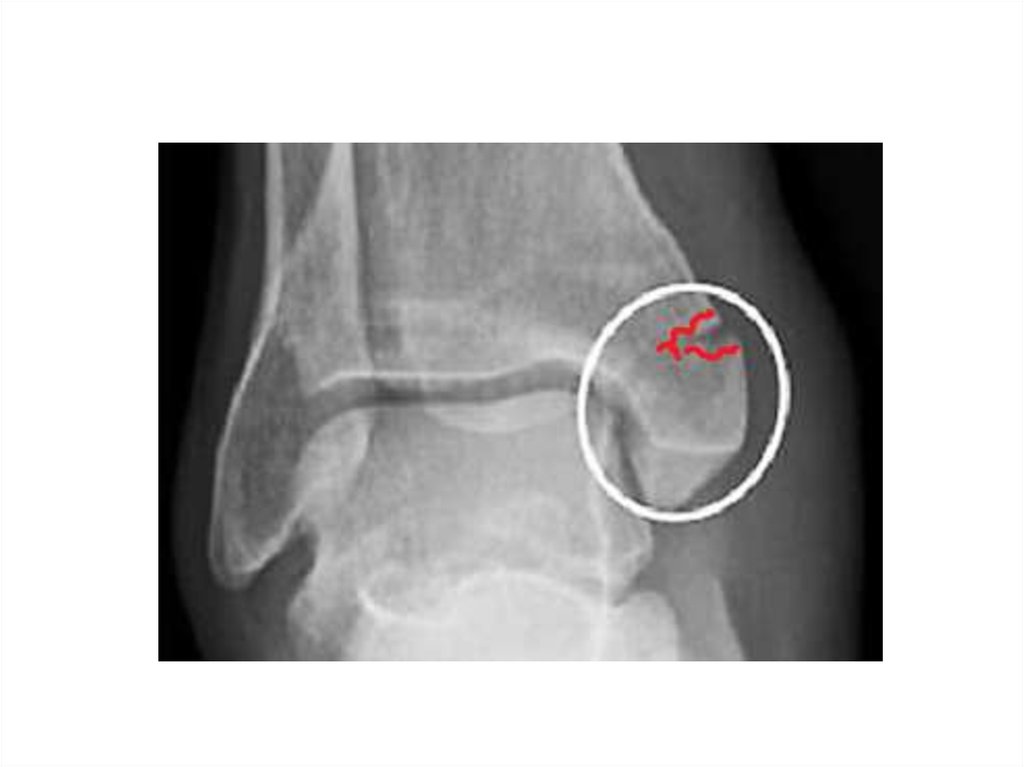

Перелом лодыжек — один из

наиболее часто встречающихся видов

травм, возникающий чаще в результате

падения во время гололеда или при

занятии спортом.

Переломы лодыжек характеризуются

нарушением анатомической

целостности:

дистального отдела малоберцовой

кости (перелом наружной лодыжки)

дистального отдела

большеберцовой кости (перелом

внутренней лодыжки).

при их сочетании говорят о

двухлодыжечном переломе.